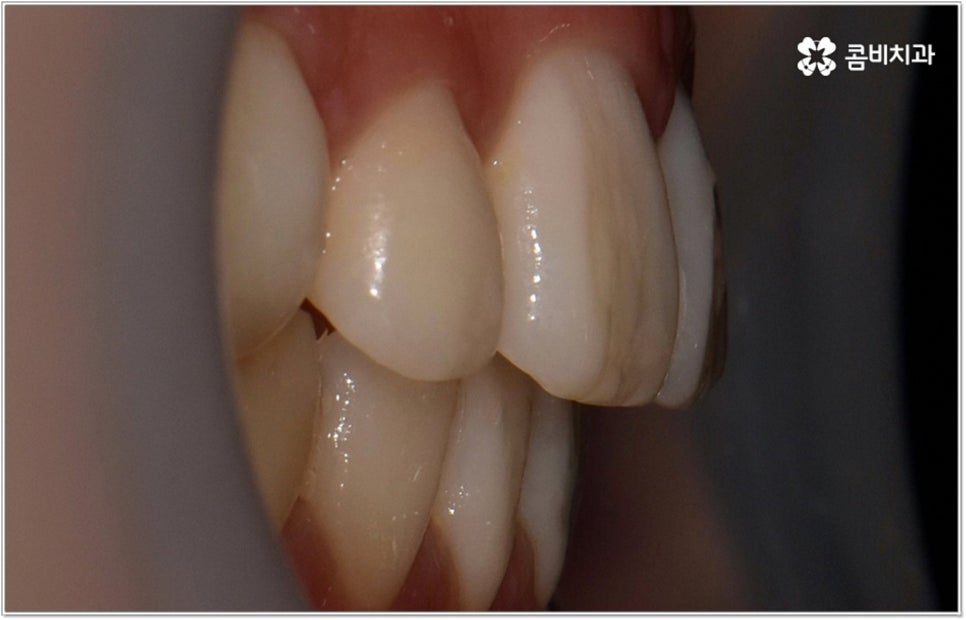

위아래 치열이 제대로 맞지 않으면 식사를 할 때 불편하고 발음이 샐 수 있습니다. 부정교합의 정도가 심하지 않아서 이러한 기능적인 문제가 당장은 크지 않다고 하더라도 성장을 하면서 잘못된 교합에 적응하고 악화되는 쪽으로 악관절이 발달한다면 불편함이 커지는 것은 물론 씹을 때 통증이 생기거나 안면비대칭 현상까지 초래할 수 있기 때문에 어릴 때부터 주의하는 것이 좋습니다

이러한 기능적인 부분 외에 심미적인 부분에서도 문제가 발생할 수 있는데요. 예를 들어 치아가 튀어나와 있다면 가만히 있어도 퉁명스러워 보이거나 화가 난 것처럼 느껴지고 입을 꼭 다물기가 어려워서 무리하게 힘을 주게 되기 때문에 입가나 턱에 주름이 질 수도 있어요. 이때 돌출입치아교정 치료를 받게 되면 위아래가 잘 맞물리는 가지런한 치열을 가지게 되는 것 뿐 아니라 자연스러운 입매와 부드럽고 균형잡힌 인상으로 바뀌게 되어 스스로 자신감 있는 태도를 가지게 되고 대인 관계에서 호감도도 높아질 거예요.